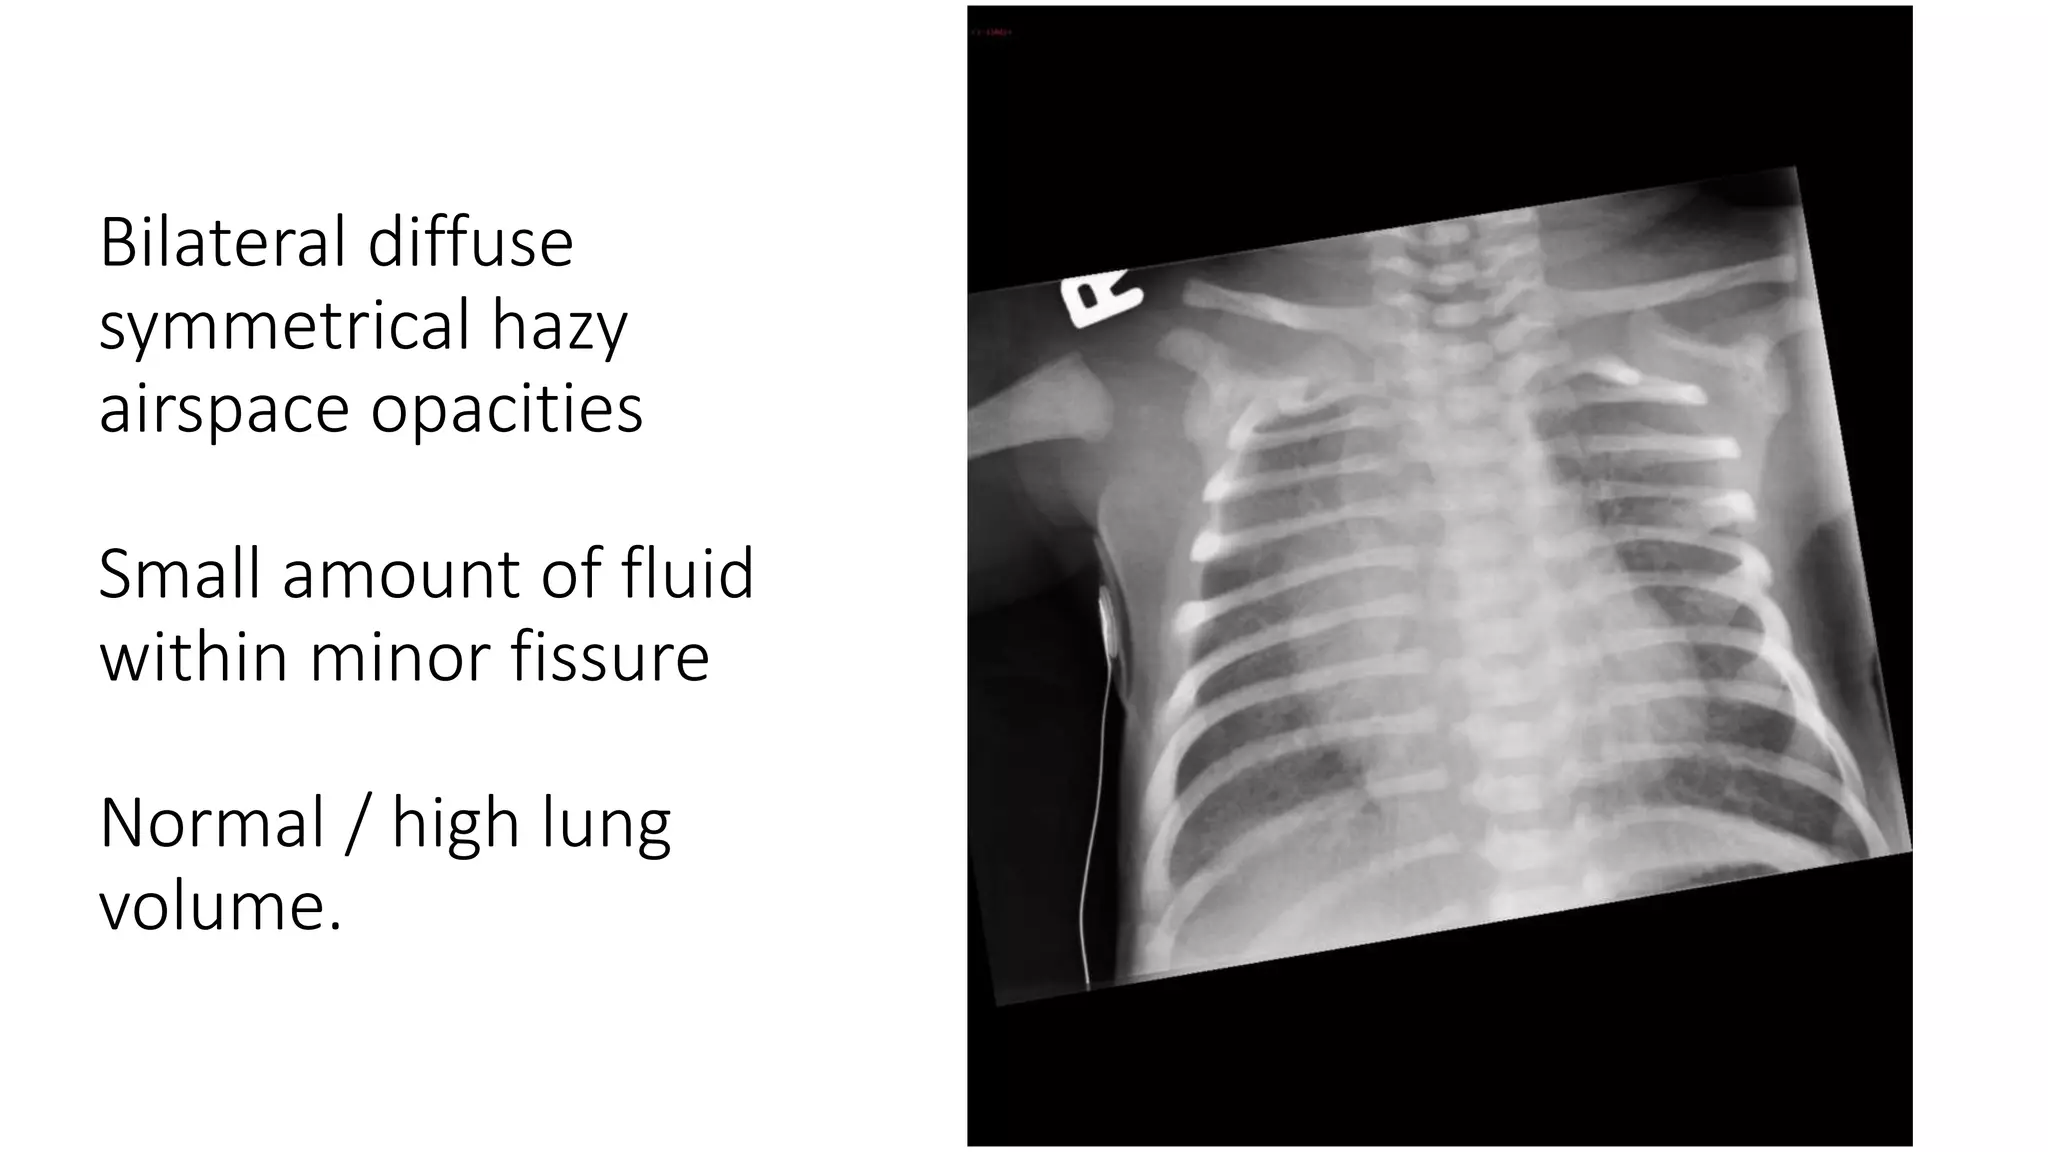

This document provides an overview of neonatal chest x-rays, including when they should and should not be performed, what a normal x-ray looks like, common positions of tubes and catheters, and common causes of respiratory distress in neonates. It discusses the appearance of a normal chest x-ray as well as conditions like respiratory distress syndrome, transient tachypnea of the newborn, meconium aspiration syndrome, and pneumonia. Surgical conditions like diaphragmatic hernia and esophageal atresia are also reviewed.